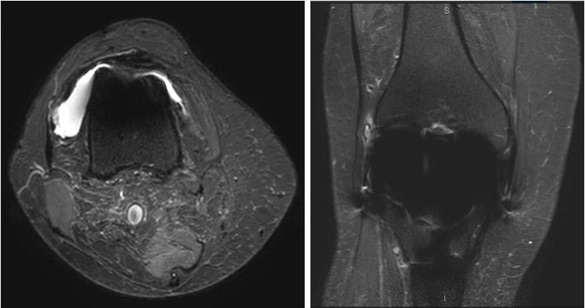

Evaluación con resonancia magnética de artroplastias totales de rodilla sintomáticas. [MRI evaluation of symptomatic total knee arthroplasties ].